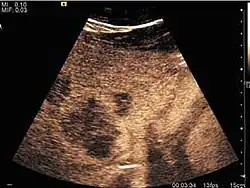

It is the most common liver tumor with a prevalence of 0.4 – 7.4%. It is generally asymptomatic but also can be associated with pain complaints or cytopenia and/or anemia when it is very bulky. It is unique or paucilocular. It can be associated with other types of benign liver tumors. Characteristic 2D ultrasound appearance is that of a very well defined lesion, with sizes of 2–3 cm or less, showing increased echogenity and, when located in contact with the diaphragm, a "mirror image" phenomenon can be seen. When palpating the liver with the transducer the hemangioma is compressible sending reverberations backwards. Doppler exploration reveals no circulatory signal due to very slow flow speed. CEUS investigation has real diagnosis value due to the typical behavior of progressive CA enhancement of the tumor from the periphery towards the center. The enhancement is slow, during several minutes, depending on the size of hemangioma and on the presence (or absence) of internal thrombosis. During late (sinusoidal) phase, if totally "filled" with CA, hemangioma appears isoechoic to the liver. Deviations from the above described behavior can occur in arterialized hemangiomas or those containing arterio-venous shunts. In these cases, differentiation from a malignant tumor is difficult and requires other imaging procedures, follow up and measurements of the tumor at short time intervals.[4]